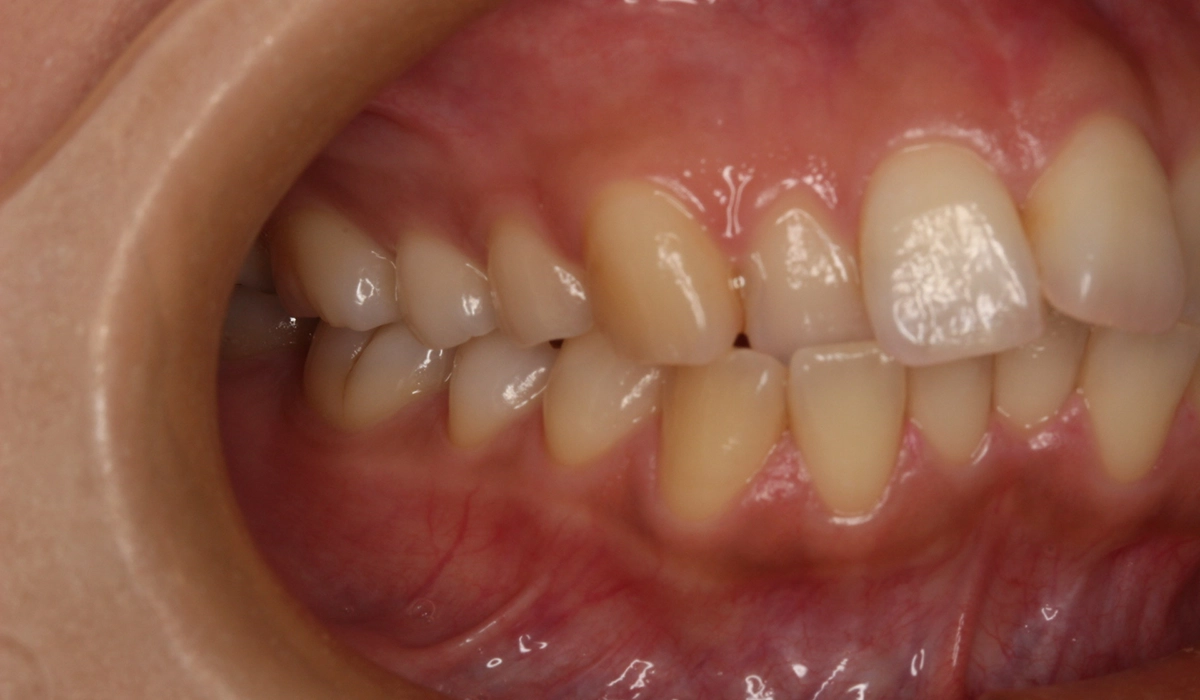

術前:右側

術前:左側

今回ご紹介する患者様は、上下前歯部のがたつきを気にされており、検査後Ⅰ級叢生と診断いたしました。左上7番予後不良により抜歯し、左上8番を配列したためやや治療期間が長くなるも満足いく配列となり患者様も満足していただけました。

| 治療内容 | 上下前歯部のがたつきを気にされており、検査後Ⅰ級叢生と診断いたしました。左上7番予後不良により抜歯し、左上8番を配列したためやや治療期間が長くなるも満足いく配列となり患者様も満足していただけました。 |